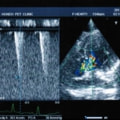

症例1:閉塞型肥大型心筋症(HOCM)【アメリカン・ショートヘア 4歳齢 去勢オス】

C:超音波写真 僧帽弁逆流と左室流出路狭窄

1年ほど前より左側胸壁からLevine 3/6の心雑音が聴取されていた。雑音の精査のため、心エコー検査を行ったところ、左室流出路の狭窄を伴う肥大型心筋症(閉塞型肥大型心筋症)と判明した。心室の拡張性を上げるため、βブロッカーであるカルベジロールを用いた治療を行っている。肥大型心筋症は犬の心疾患のように、心拡大を認めないことも多く、レントゲン写真のみで心疾患の有無を判断する事が出来ない。また、閉塞を伴わない肥大型心筋症と異なり、閉塞型の本疾患の治療に対し、Caチャネルブロッカーは推奨されない。